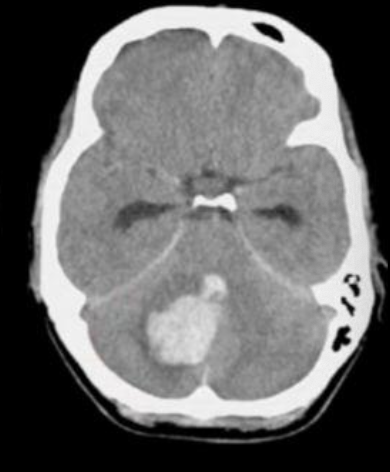

EVC hemorragico 36 horas